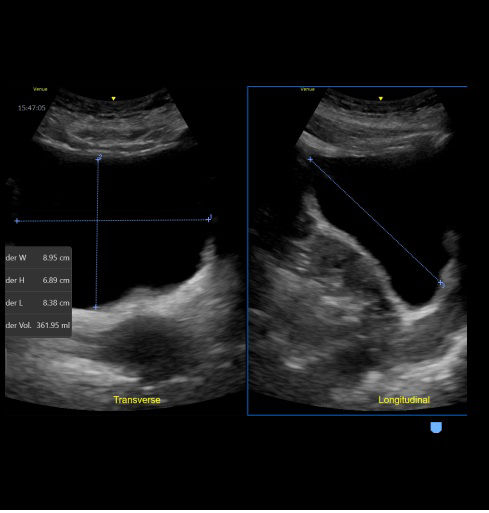

Quick and easy bladder volume documentation

The Bladder Volume Tool is a simplified workflow tool featuring reference images as guidance and supports clinicians in calculation of the bladder volume. The tool is designed to guide bladder volume measurements to make it simple and fast.

feature-card-full-width-bladder-volume-desktop crooped 1